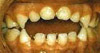

Kieferengstand

Beim Kieferengstand ist die Kieferbasis zu klein, so daß die Zähne

nicht den benötigten Platz finden können, um in einem geraden Zahnbogen

zu wachsen. Deshalb treten Kieferengstände meist mit mehr oder weniger

starken Fehlstellungen auf.